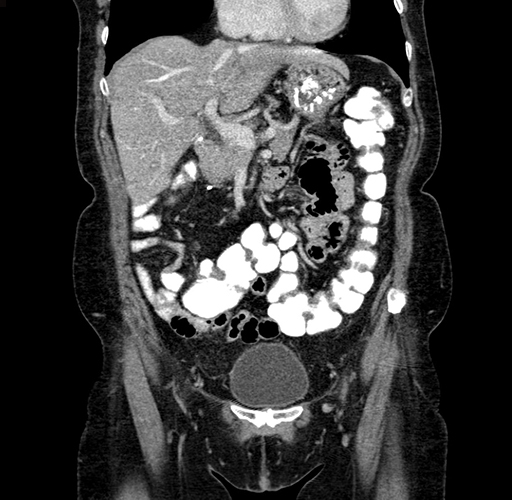

Axial Venous